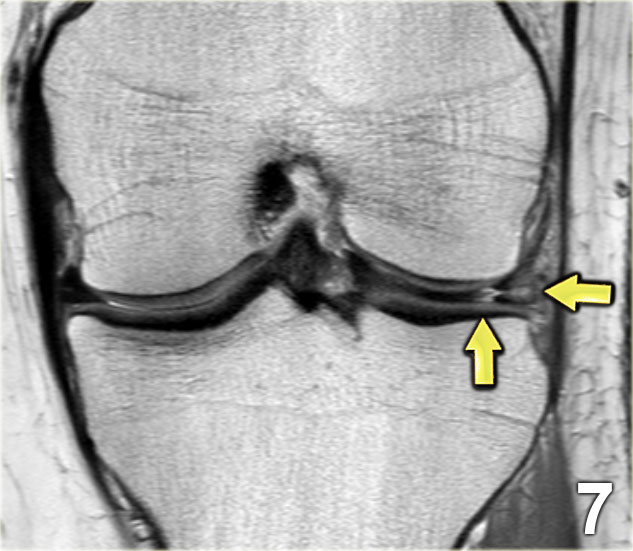

Cấu trúc giảm tín hiệu ở phía bên ngoài (lateral) là sụn chêm hình đĩa (mũi tên xanh).

Cấu trúc ở phía trong (medial) là hiện tượng chân không (vacuum phenomenon).

Trên lát cắt liền kề, hiện tượng chân không này không còn được quan sát thấy nữa.